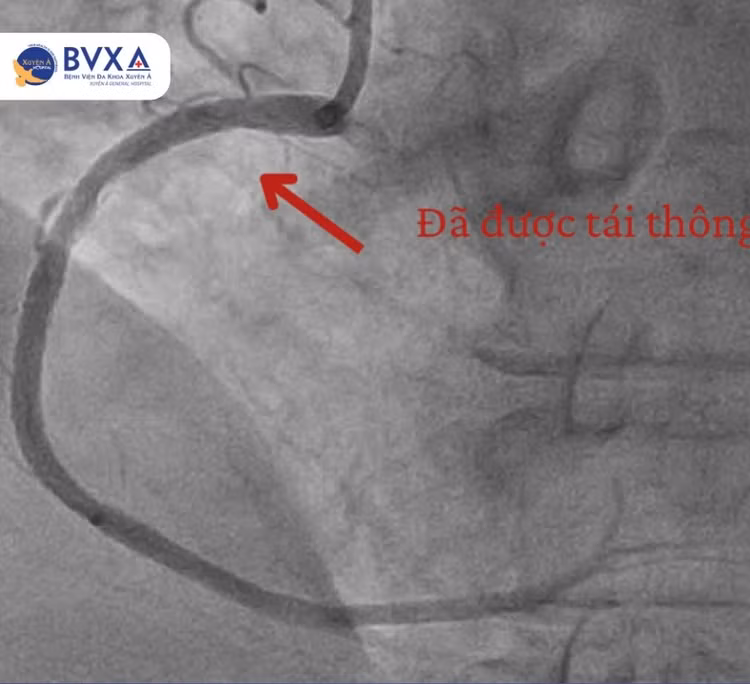

| Hình ảnh vị trí đoạn mạch bị tắc - Hình ảnh sau khi thông - Ảnh BVCC |

Dựa trên kết quả chụp mạch vành, các bác sĩ phát hiện người bệnh bị tắc hoàn toàn đoạn gần của động mạch vành phải. Trước tình hình này, ê-kíp bác sĩ khoa Can thiệp Tim mạch đã tiến hành can thiệp nong và đặt stent tại vị trí tắc mạch.

Chỉ sau 45 phút, một stent đã được đặt thành công giúp dòng máu tái thông hoàn toàn. Sau vài ngày theo dõi, điều trị tại khoa Nội tim mạch, tình trạng người bệnh dần ổn định, phục hồi rất tốt, được xuất viện và tái khám định kỳ theo hướng dẫn của bác sĩ.